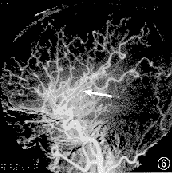

患者女,28岁。因突然发生左眼视3天,于1998年8月2日入院。入院后3天亦发生右眼视。发病初期患者曾有一过性头痛,双眼左侧视物障碍,检查视力双眼均为1.2,无昏迷、呕吐,无肢体和面部的偏瘫及知觉丧失,无语言障碍。体检未见异常。眼部检查:右眼视力1.2,左眼1.5。双眼球运动正常,眼前节及屈光间质正常。散瞳检查眼底:双眼视乳头边界清晰,视网膜无出血、渗出,视网膜动静脉比例正常,黄斑区无水肿,中心窝反光存在。辅助检查:头部CT扫描及增强扫描未见异常;TBC微机中心视野计检查及周边弓形视野计检查,示双眼左侧一致性偏盲,有黄斑回避。于同年8月27日由颅脑外科经右侧腹股沟穿刺行全脑血管造影术(图1~6)。诊断:右大脑后动脉阻塞;右大脑前动脉先天性缺如。

图5 右颈动脉正位片,示右大脑前动脉主干支完全缺如

图6 右颈动脉侧位片,与左颈动脉造影侧位片相比,血管呈代偿性增生